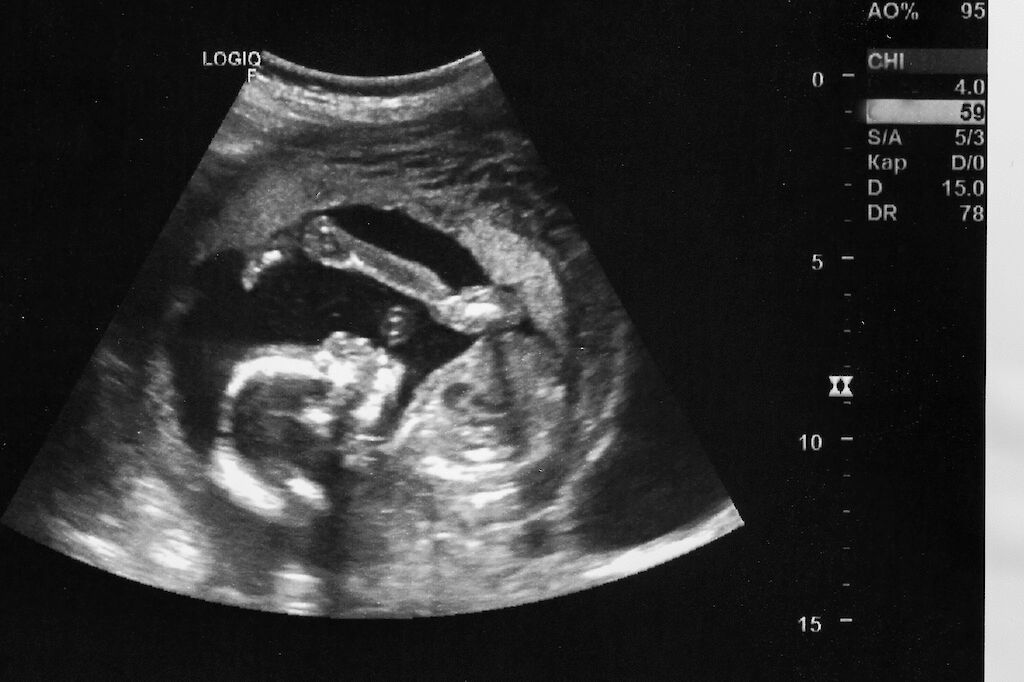

Tutkimuksiin kuuluvat keski- ja loppuraskauden ultraääni, sikiön yleisvoinnin kuvantaminen sekä kasvun mittaaminen.

Listoilta löytyvät myös sikiön liikelaskenta, lapsiveden määrän arviointi ja jopa synnytystapa-arvio.